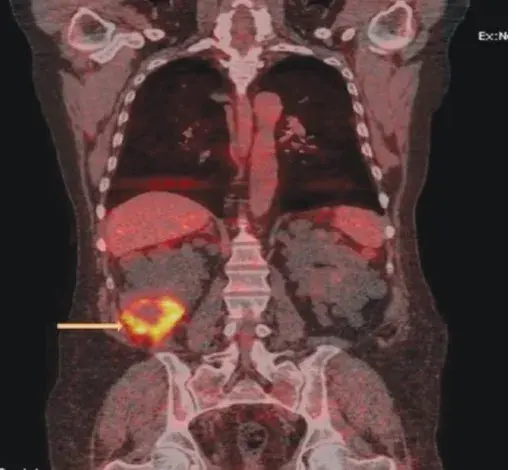

Proteinúria refratária em paciente com Nefrite Lúpica

Caso muito ilustrativo publicado no Kidney 360 (link) Paciente do sexo feminino com 43 anos e com antecedente de nefrite lúpica (NL) proliferativa há 13 anos. A paciente apresentava histórico de acometimento grave da doença, com múltiplos tratamentos com infusões de metilprednisona e ciclofosfamida devido ao acometimento do sistema nervoso central (SNC) e da NL.